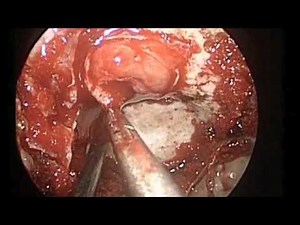

Transsphenoideal Removal of Pituitary Tumor • Video • MEDtube.net

medtube.net

Jan 31, 2015